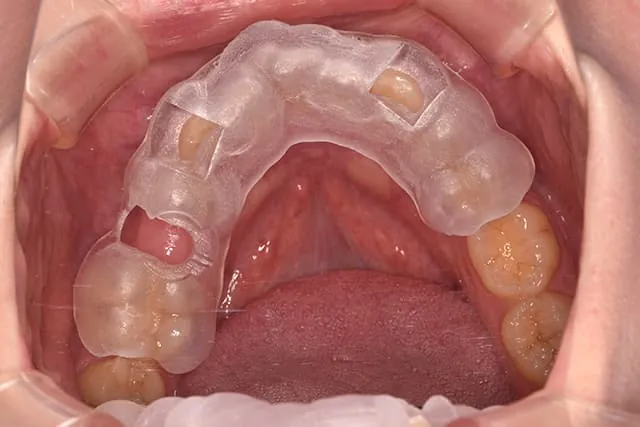

実際の症例写真

マウスピース状のガイド装置をセットして埋入します

術後はほぼ出血もなく、痛みもでにくくなります